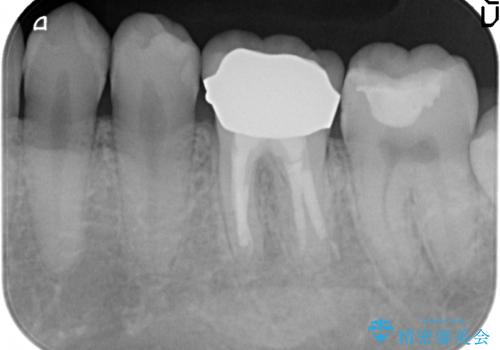

放置してしまった歯 根管治療からの機能回復

- 放置してしまった歯が痛み、いよいよ耐えられなくなり来院されました。

根管治療の途中で放置してしまっていた歯を、最終的に機能回復できるよう治療を行っていきます。